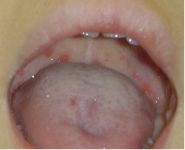

上あごの奥に発疹、水疱、潰瘍ができます。

これが見られれば診断は容易です。

診察の最後に咽喉をのぞいてみて、

写真のような発疹を上あごに見つければ、すぐにヘルパンギーナとわかります。